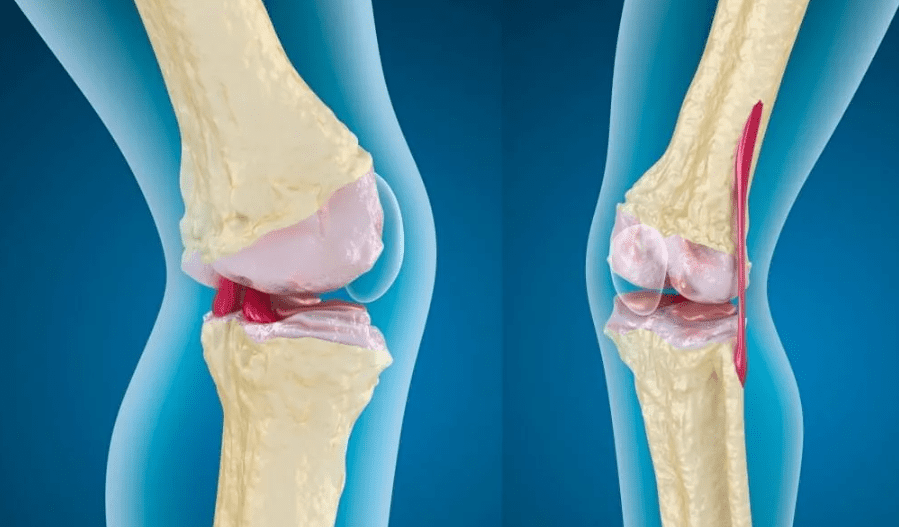

Загострення остеоартрозу супроводжується посиленням болю, відчуттям скутості після відпочинку та набряками в ділянці суглоба. У цей період важливо не зволікати з діями, аби запобігти подальшому руйнуванню хрящової тканини. Допомогти зменшити симптоми можуть прості кроки, які варто знати кожному: